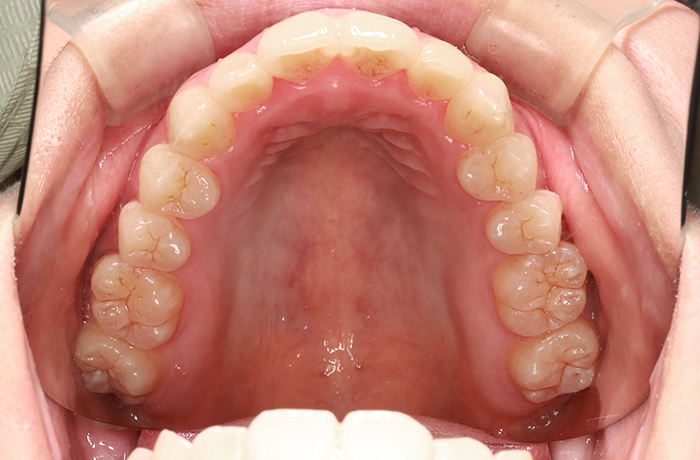

治療後

after

患者の症状 叢生、正中のずれ、上顎左右側切歯の口蓋側転位(交叉咬合)

治療方法 非抜歯で、マウスピース型カスタムメイド矯正歯科装置(インビザライン)による矯正

歯列弓を拡大することで非抜歯を可能にしました。

治療結果 側切歯の交叉咬合は解消、上下正中のずれも改善し咬み合わせが良くなりました。